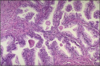

Immature (seen below) : incomplete differentiated

Teratoma